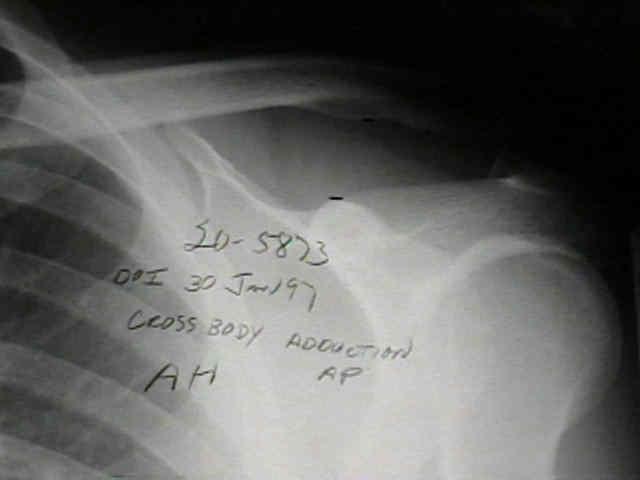

• Cross Body Adduction View

• (from C.J. Basamania MD personal communication, 1997);

• 20-year-old who fell on tip of right shoulder, but did not show radiographic signs of AC joint injury in the ER;

• one month later the patient continued to have pain, and radiographs demonstrated greater than 100 percent displacement of AC joint on both AP and Cross Body AP (Cross Adduction View);